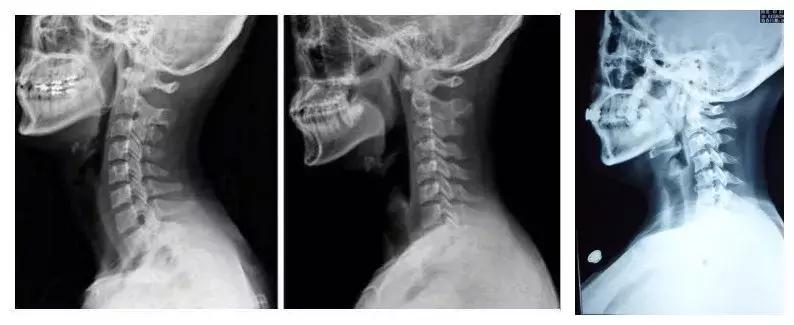

养护:大部分患者都会有颈椎生理曲度变直或者反弓,这都是低头惹的祸。